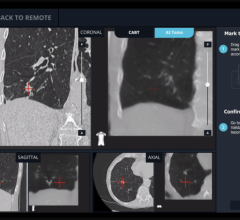

Ziehm’s Object Detected Dose Control feature for the Vision line of C-arms purportedly improves image quality with a low dose while also making the system easier to handle. The new real-time image control covers the whole field of view and provides independent object positioning within the field.

The tool allows real-time motion detection, which adjusts the noise reduction level whenever there are moving objects. The system also reduces the pulse frequency in the case of non-moving objects. The new tool also features automatic metal correction to reduce the blooming effect, to produce optimal image quality even when there is metal in the image.